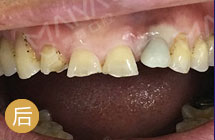

直播女主杨阿姨:我为麦芽口腔点赞

手术成功原理:借助锥形束CT判断牙槽骨骨量与骨壁厚度,重建口腔制作3D导板,微创拔除断折前牙同时借助导板完成植体植入,同期安装牙冠,形成良好的美学效果… [详细]

拔牙同时就种牙

少做手术少遭罪

避免延期骨量萎缩

不植骨更省钱